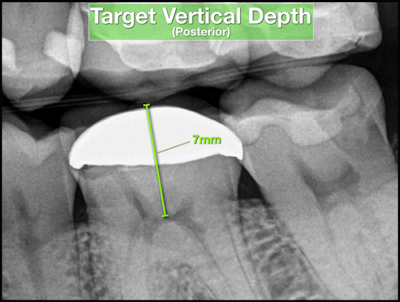

Before initiating treatment, an estimate can be made from the tooth’s occlusal surface (or incisal edge) to various levels within the tooth. This estimate represents a “target vertical depth” and can assist with endodontic access when measured to the roof of the pulp chamber (Fig. 1). In multi-rooted teeth, an additional “terminal depth estimate,” measured to the furcation, could help avoid iatrogenic perforation (Fig 2).

A bitewing radiograph is considered to be the most spatially accurate and dimensionally stable image with respect to 2-dimensional radiography, making it ideal to estimate the depth when treating posterior teeth. Estimates for anterior teeth must be determined from the slightly more distorted periapical radiograph (Fig 3). This visual exercise can also influence case selection.